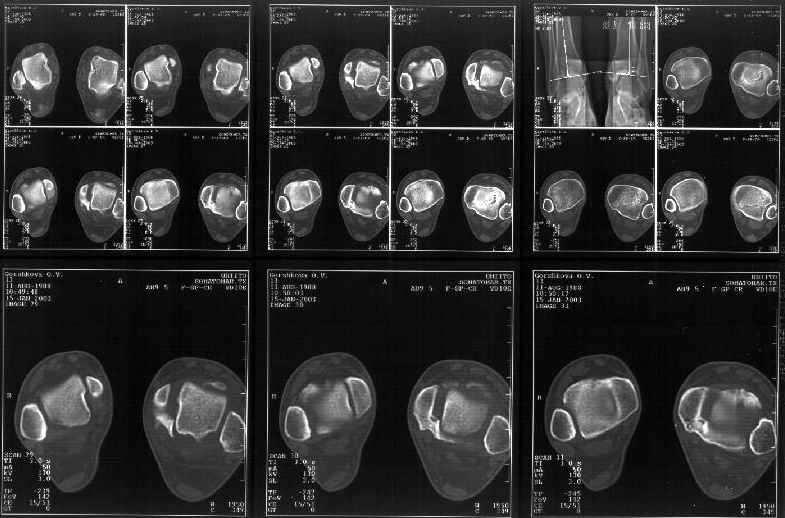

На следующий день пациентке сделали КТ. Может быть, после просмотра картинки будут другие предложения? Не убрать ли ве-таки этот фрагмент

позади внутренней лодыжки, который оттесняет таран кнаружи?

Думаю, КТ прочитан не верно. Задняя часть медиального маллеола, в сущности уже часть заднего маллеола стоит на месте и трогать её не следует. Передняя часть маллеола на 3-4 мм удалена от тарана. Сравните с пространством между

латеральным маллеолом и тараном. В норме все три должны быть одинаковы: между тараном и латеральным, задним и медиальным. Это главное условие устойчивого сидения тарана в голеностопном суставе.

Все-таки она как раз была была отколота и вместе с тараном смещена латерально.

Внутренняя лодыжка не была сломана, она как была на своем месте, так там и находится. Это таран от нее отдавлен кнаружи смщенным в его сторону фрагментом позади внутренней лодыжки. За счет чего и есть проявления нестабильности связок.

Мне в тоже время совершенно ясно видно по той же КТ, по 4 срезам, расположенным в центре и вверху пленки, что перелома внутренней лодыжки не было, в следующем собщении я приложу увеличенный фрагмент томограммы. А к этому письму прилагаю увеличеный фрагмент послеоперационной рентгенограммы, где выделил отколотый фрагмент

позади внутренней лодыжки. И он, как я вижу, находится между стержнем и тараном. А перелома внутренней лодыжки, и тем более смещения, IMHO

не определяется.

Отправитель: Alexander Chelnokov 12 Январь 2003, 14:55

Здесь 4 среза, начиная от основания лодыжки и проксимальнее. Где, по Вашему мнению, проходит линия перелома, отделяющая переднюю часть внутренней лодыжки от большеберцовой кости? Заранее спасибо.

Я пометил линию перелома черной линией.

К сожалению на последних присланных срезах КТ нет более низкого, через таран, среза, который был на прежнем майле. На XR я попытался показать

стержень внутри сустава и то как он раскрывает пространство между тараном и мед. малеолом.